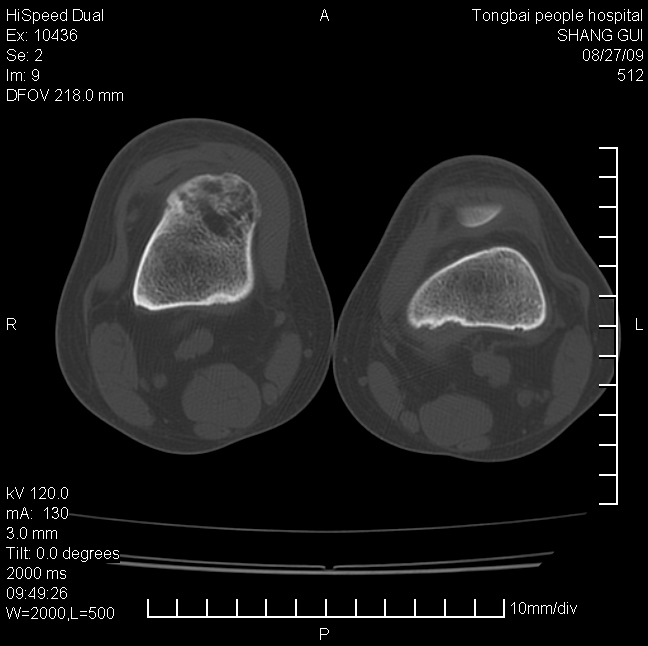

女,12岁。无意发现股骨下端隆起。局部皮肤颜色,温度无异常。

不能排除,其实平片更直观。宽基底骨软骨瘤皮质与骨干皮质相连,髓腔与髓腔相通,骨纹理走行方向一致,部分软骨帽可有钙化,本例病变内“磨玻璃状、多囊状改变”比较符合骨纤。